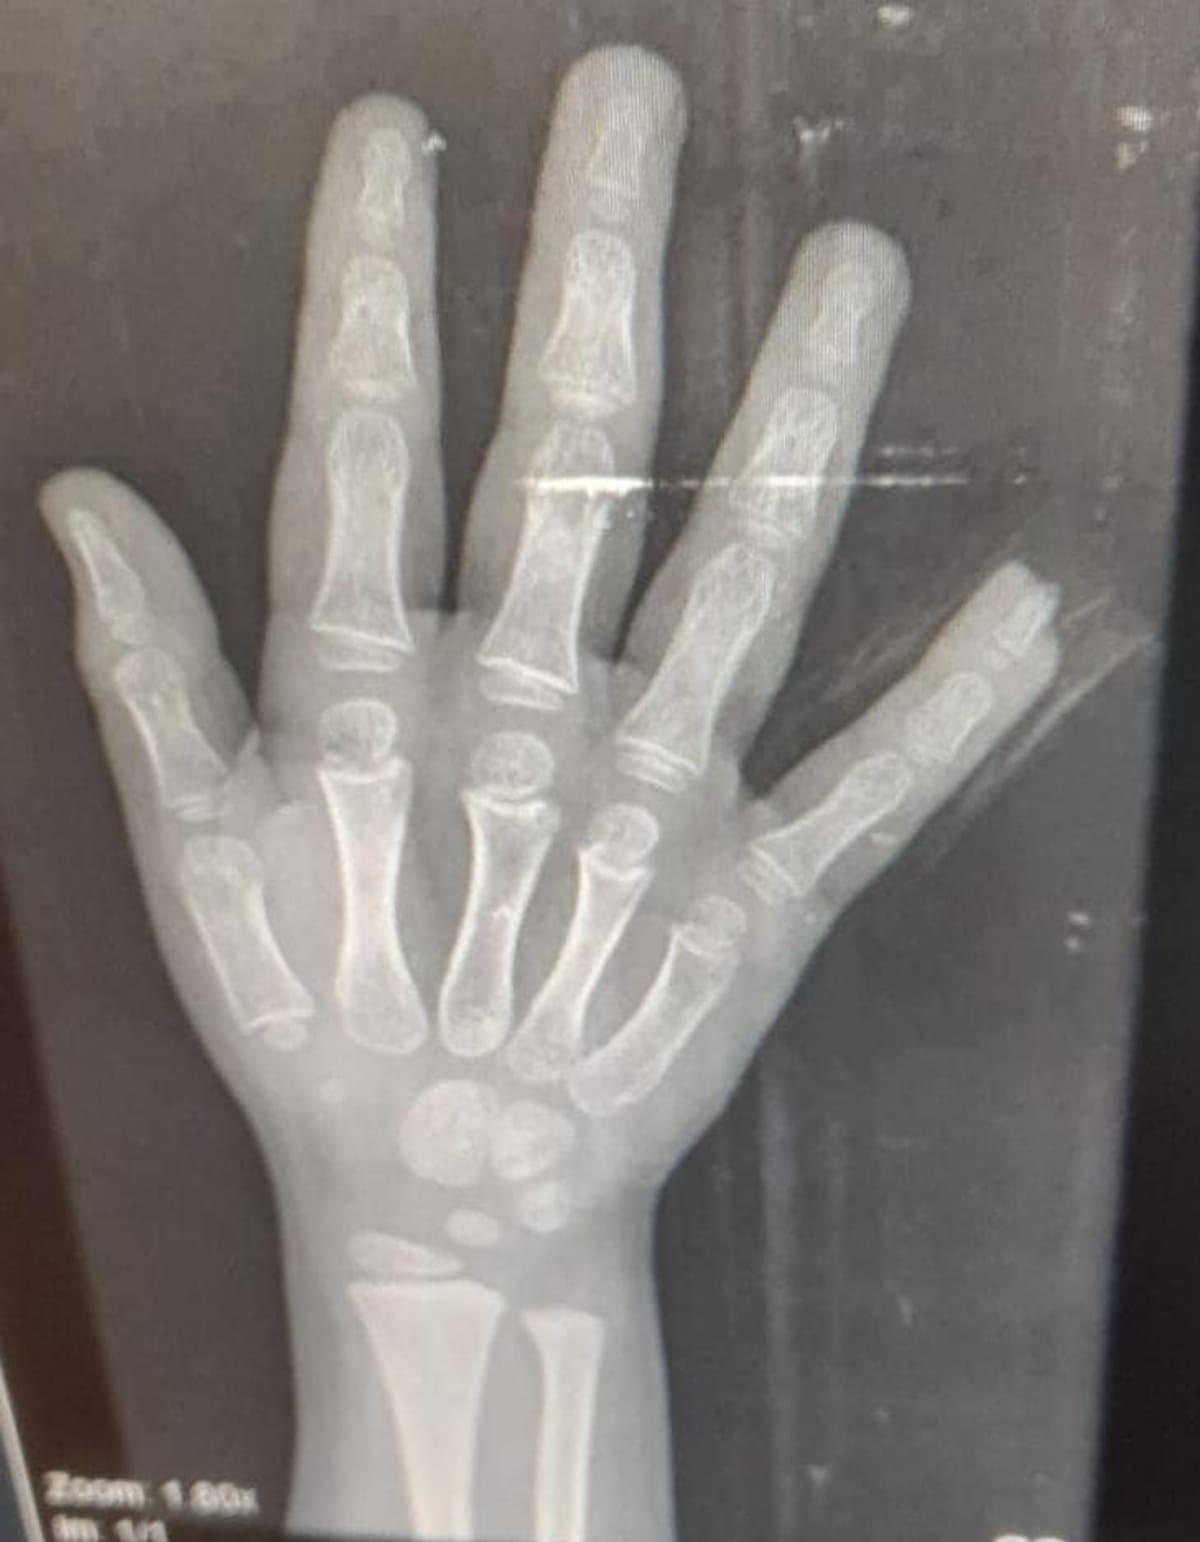

Al llegar al centro médico se confirmó que el menor no tenía una cortada sino había sufrido la amputación de la falange del quinto dedo de la mano izquierda (meñique) tras quedar aprisionado con la puerta de un baño.

Al niño se le practicó una cirugía en el dedo y 30 días de incapacidad. Mientras tanto los padres piden a las autoridades la investigación de lo sucedido.